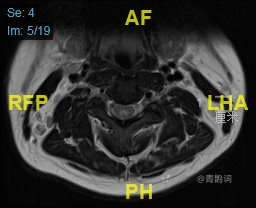

颈部磁共振平扫:

颈部磁共振平扫后增强: